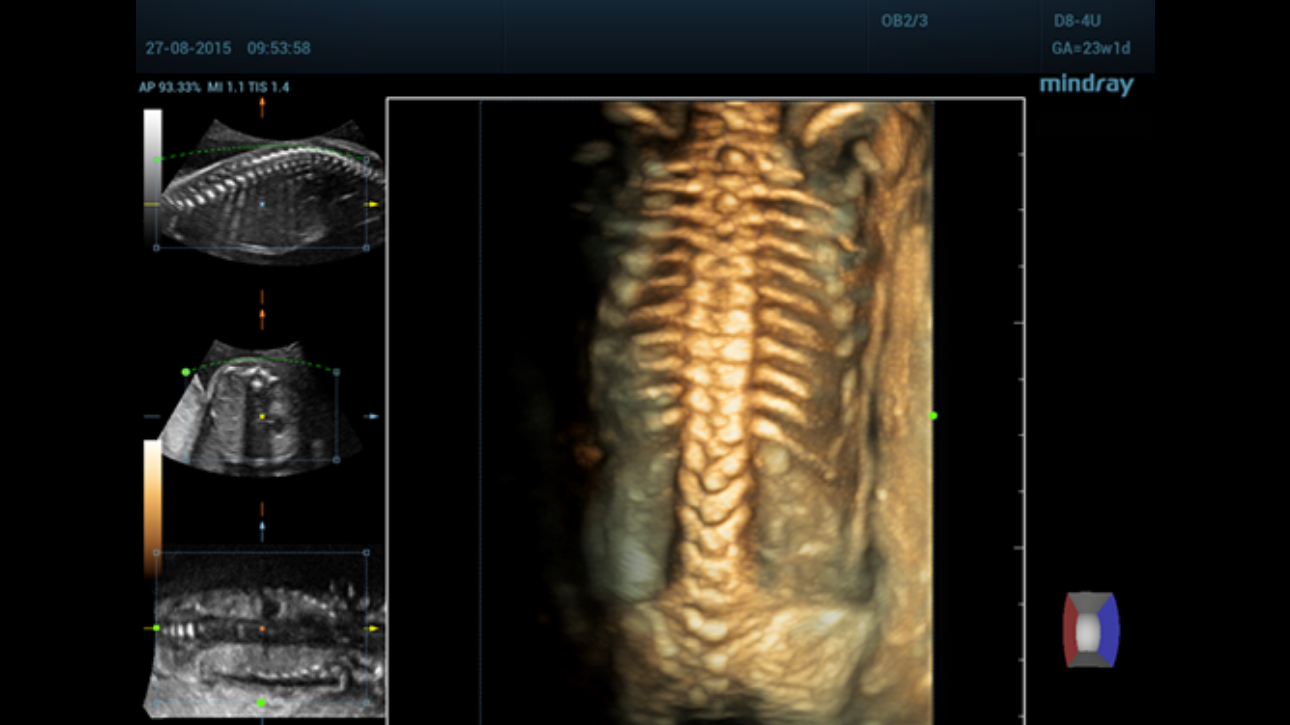

The channel data based ZST+?is an extraordinary innovation, representing an ultrasound evolution. Transforming ultrasound metrics from conventional beamforming to channel data based processing, ZST+?is more powerful and flexible to integrate the latest innovative OB/GYN imaging technologies, and to deliver a higher level of imaging performance in 2D, 3D/4D, and even the coronal plane image.

Comprehensive upgrading on iLive to significantly improve the detailed resolution as well as anatomical realism. Hyaline is a new rendering method that dynamically applies transparency to rendered structures for a more comprehensive view of anatomy, therefore better displaying internal anatomy from a solid surface.